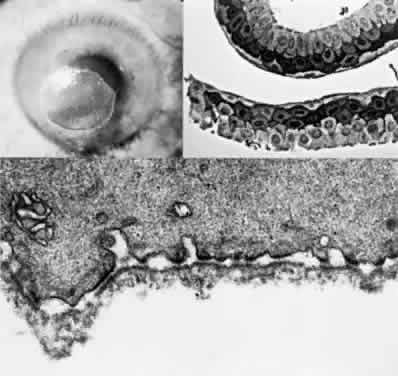

OCULAR FINDINGS. The outstanding clinical feature common to all three phenotypes is the corneal and conjunctival cystine crystal deposition (Figs. 3 and 4). Photophobia is often the only presenting visual symptom; this may be incapacitating and associated with blepharospasm.

Fig. 3. Cystinosis. Refractile crystals noted throughout the corneal stroma.

Fig. 4. Cystinosis. Top, Transmission electron micrograph showing a stromal keratocyte containing a number of needle-shaped crystalline profiles limited by unit membranes. (× 19,000.) Bottom, Electron micrograph of conjunctival fibrocyte revealing crystalline profiles of sparse granular material within membrane-limited lysosomes. (× 30,000.) (Courtesy of Dr. Kenneth Kenyon)

Corneal deposits appear as a layer of homogeneously distributed, fusiform or needle-shaped, iridescent crystals situated in the stroma beneath the epithelium. In the infantile form, anterior crystal deposition begins early in life (between 6 and 15 months of age) and proceeds posteriorly as the patient ages; deposition advances more rapidly in the periphery. The anterior location of the crystals may be associated with recurrent erosions.33 The depth of the stromal deposition and the density of crystals is always greater peripherally than centrally. More and larger crystals occur in the superficial stroma. No visual impairment occurs at this early stage. By the age of 7 years, most patients have crystals, either within or on the endothelial surface34,35; markedly decreased corneal sensitivity is also present.36 The spherical contrast sensitivity function is significantly lower in infantile cystinosis than in age-matched controls.37

The conjunctiva has a ground-glass appearance. Polychromatic, polymorphic, rectangular, or rhomboidal crystals can be seen with the biomicroscope.